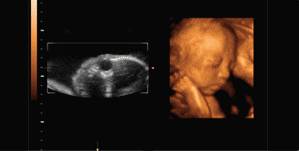

NO.3【三维彩超】

三维彩超就是将二维图像合成模型,透过屏幕可从各个方位观察胎宝宝。

但是,三维彩超虽是立体成像,但图像仍以图片形式观察,观察面为局部,且清晰度稍差于四维彩超。

NO.4【四维彩超】

四维彩超是目前世界上最先进的彩色超声设备,是采用三维超声图像加上时间维度参数,更直观更清晰地呈现胎儿在宫内的动态图像,多方位、多角度地观察胎宝宝的生长发育情况,还能够对孕期潜藏的各类疾病进行精确检测。